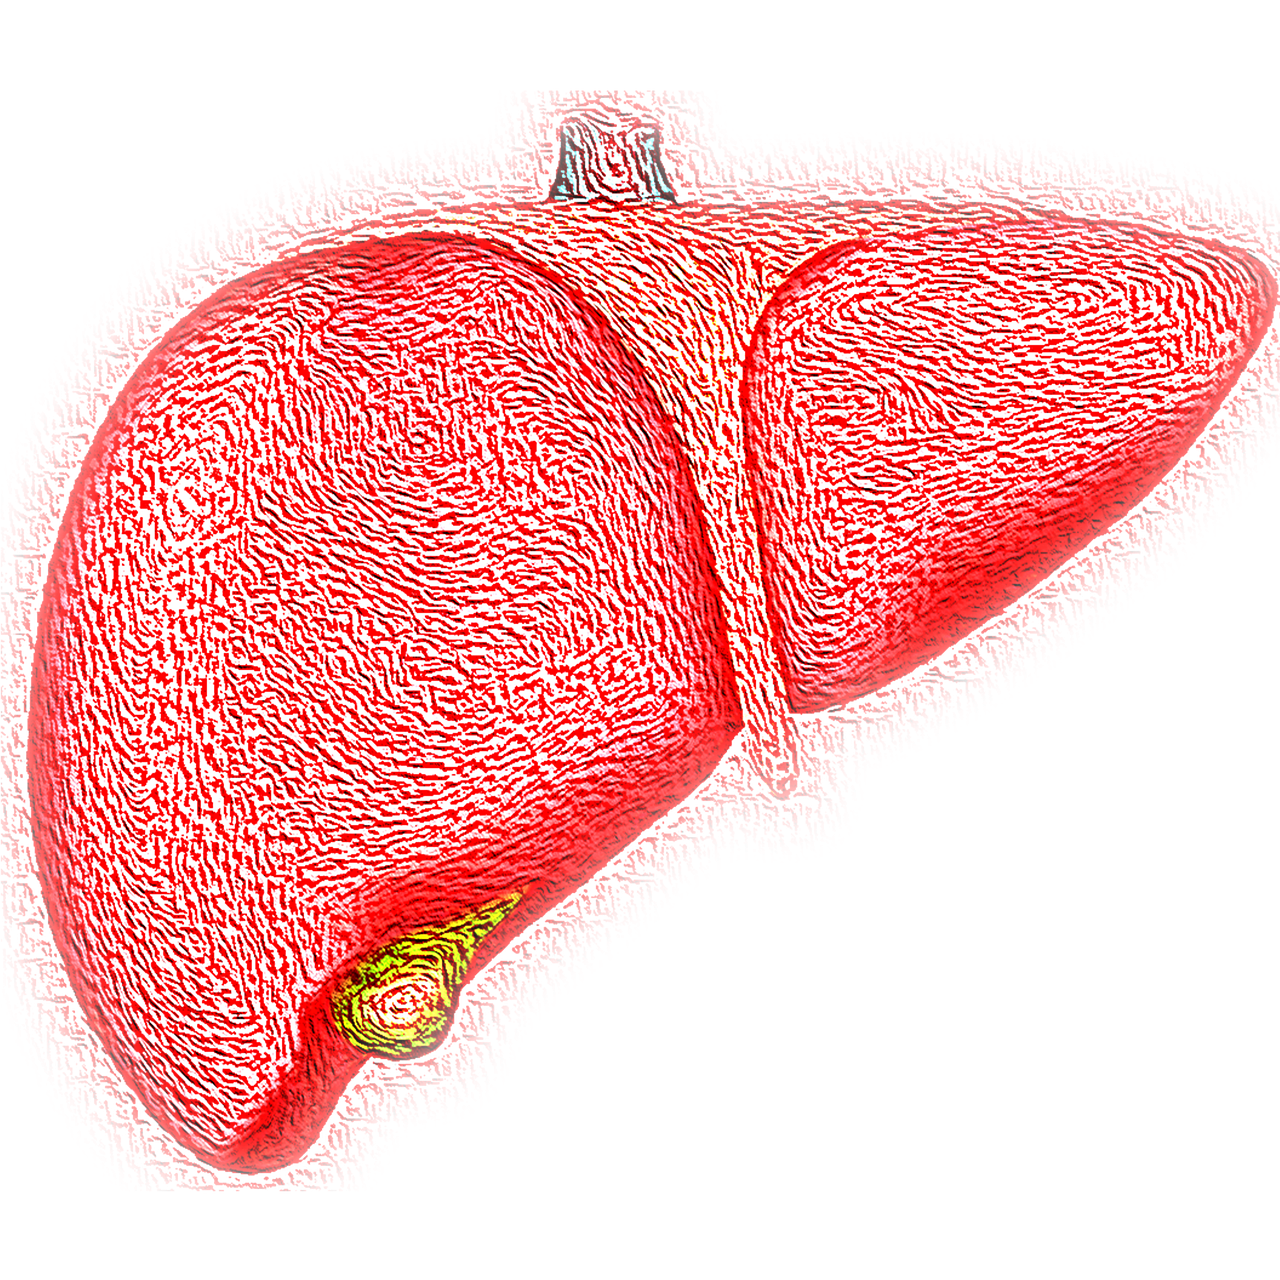

간 건강의 중요성

간은 우리 몸에서 매우 중요한 역할을 해. 음식에서 영양소를 흡수하고, 해로운 물질을 제거하는 등 다양한 기능을 수행하지. 그래서 간이 제대로 기능하지 않으면 전체적인 건강에 큰 영향을 미칠 수 있어.

간 질병의 원인

간 질병은 여러 가지 원인으로 발생할 수 있어. 주로 잘못된 식습관, 과도한 음주, 스트레스, 비만 등이 주요 원인으로 꼽히지. 이 외에도, 간에 과도한 지방이 축적되는 지방간 바이러스에 의한 간염, 간세포가 파괴되는 간경화등 다양한 질병들이 있어.